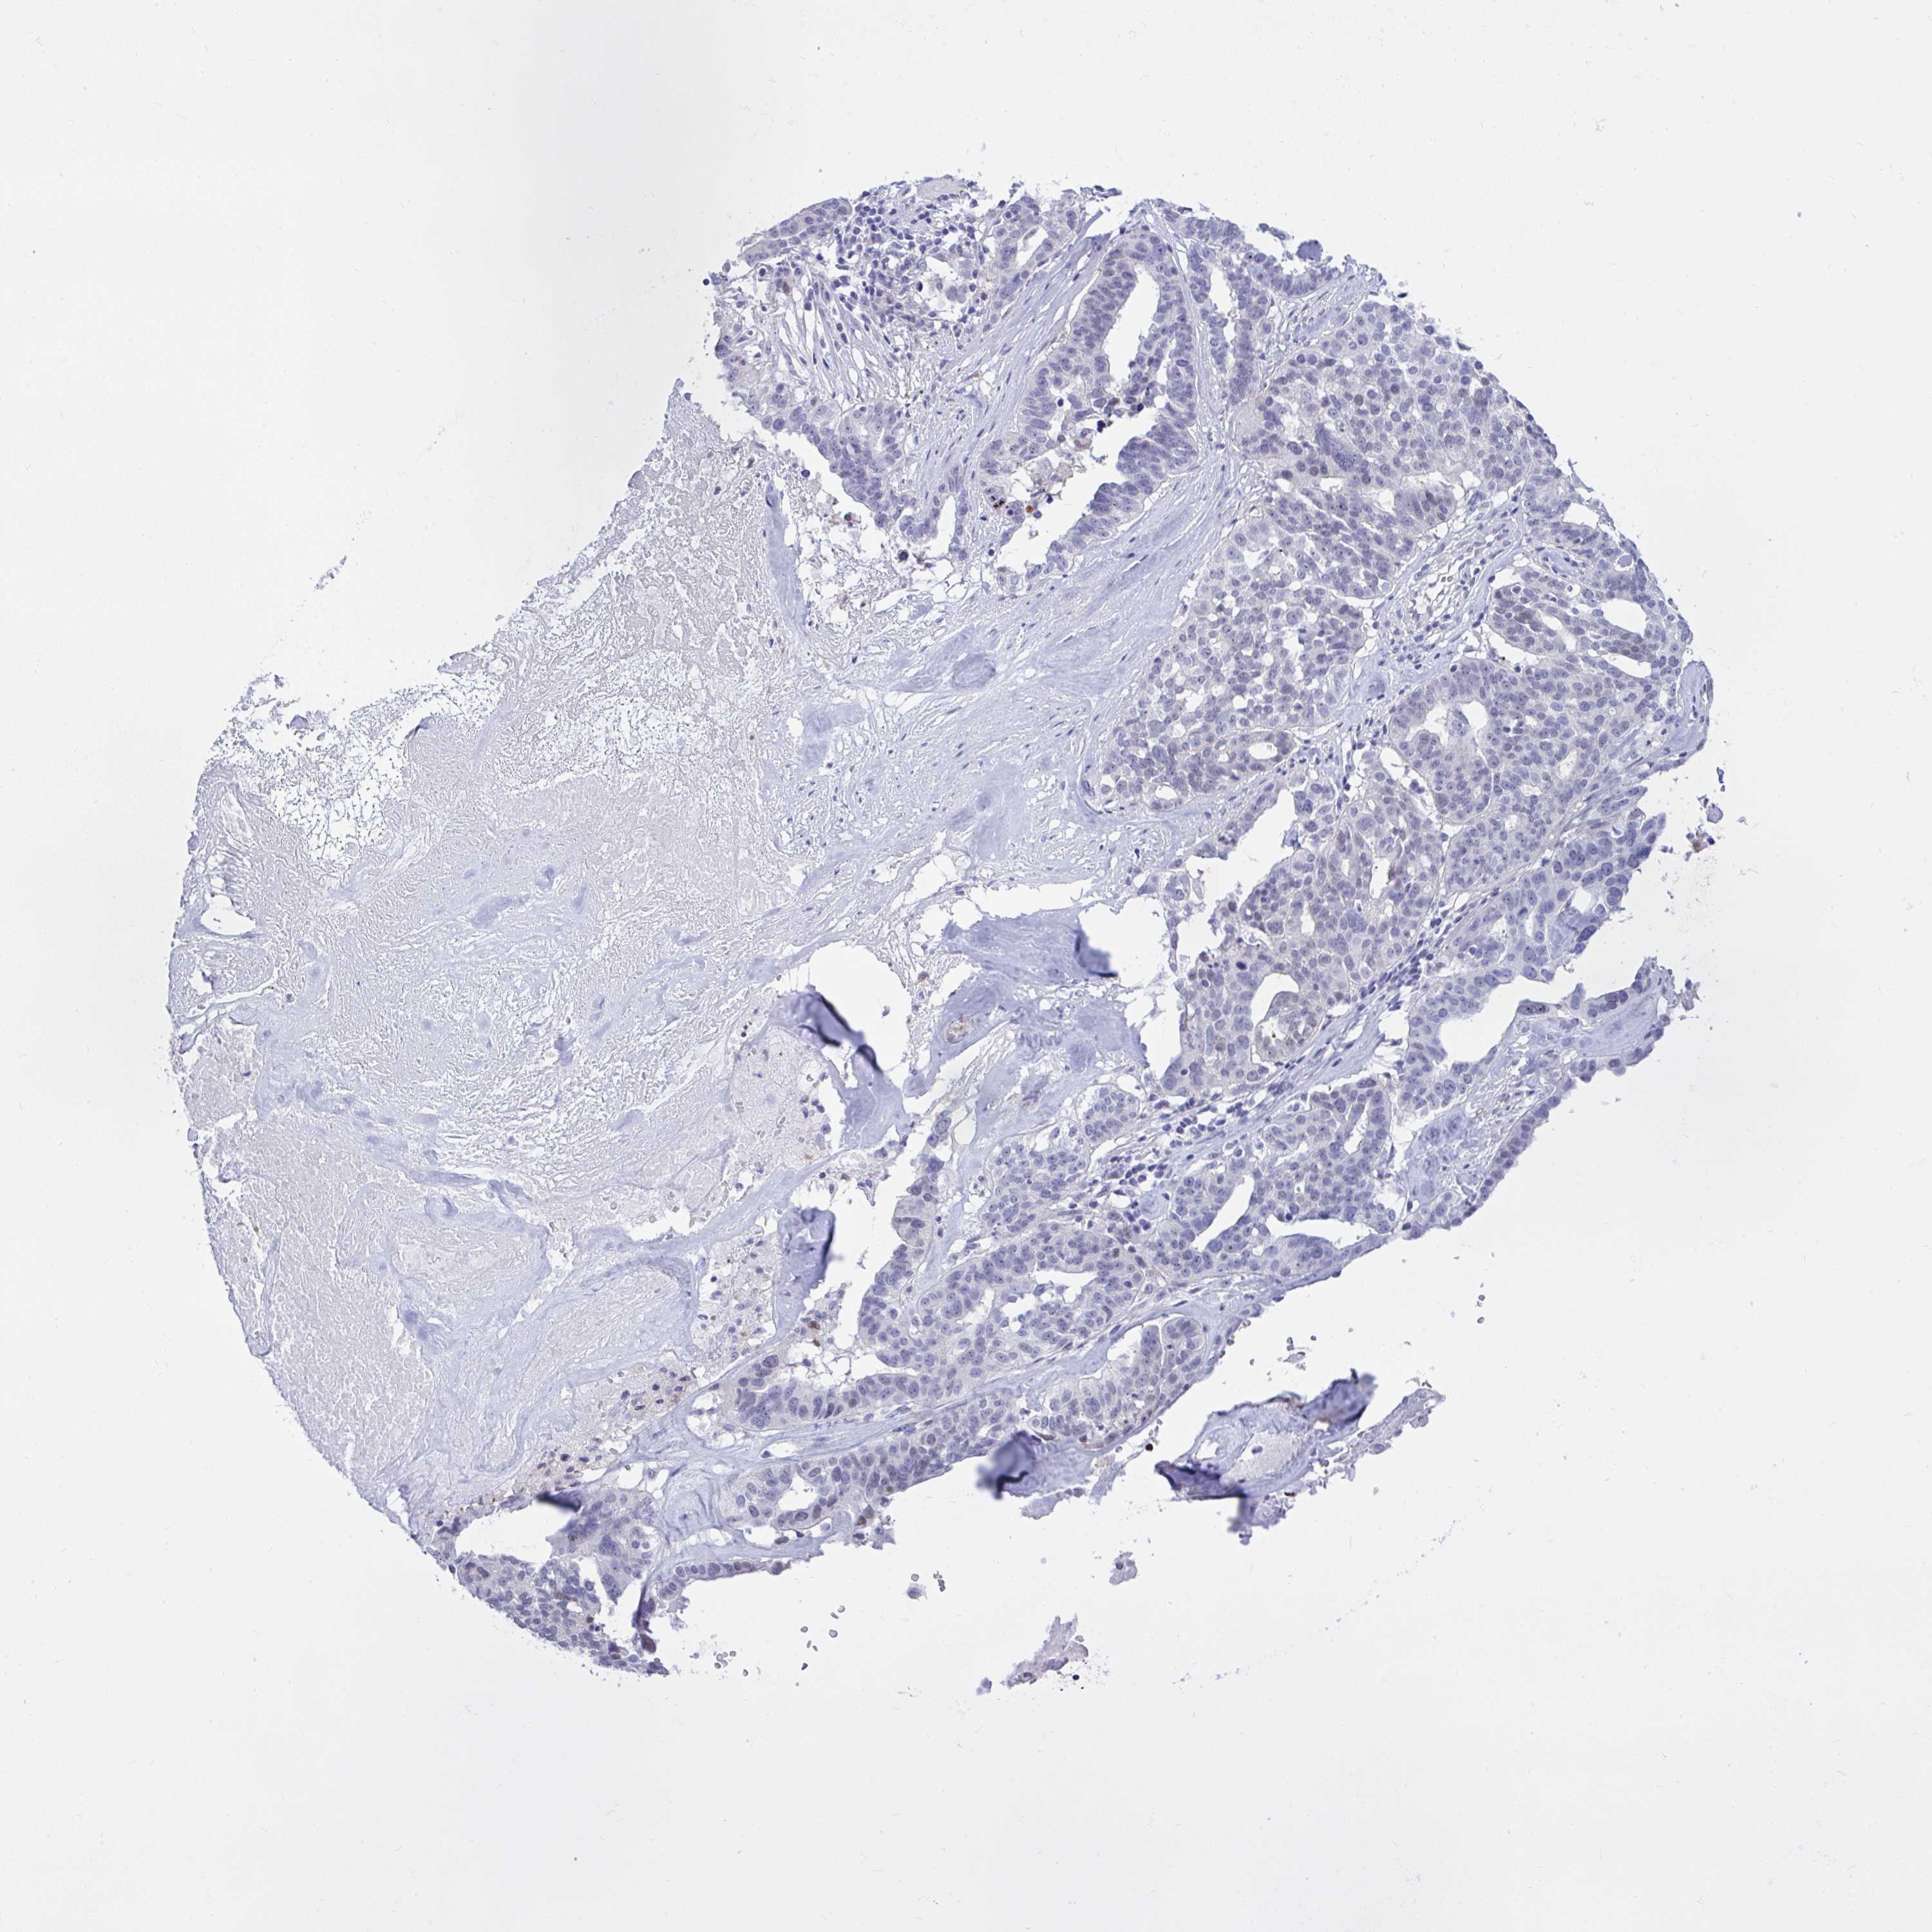

OVARIAN CANCER - Protein expressioni

A mouse-over function shows sample information and annotation data. Click on an image to view it in a full screen mode. Samples can be filtered based on level of antibody staining by selecting one or several of the following categories: high, medium, low and not detected. The assay and annotation is described here.

Note that samples used for immunohistochemistry by the Human Protein Atlas do not correspond to samples in the TCGA dataset.

Antibody stainingi

Antibody staining in the annotated cell types in the current human tissue is reported as not detected, low, medium, or high, based on conventional immunohistochemistry profiling in selected tissues. This score is based on the combination of the staining intensity and fraction of stained cells.

Each image is clickable and will lead to virtual microscopy that enables deeper exploration of all samples and also displays staining intensity scores, fraction scores and subcellular localization as well as patient and tissue information for each sample.

Antibody HPA059356

Staining

High

Medium

Low

Not detected

Intensity

Strong

Moderate

Weak

Negative

Quantity

>75%

75%-25%

<25%

None

Location

Nuclear

Cytoplasmic/membranous

Cytoplasmic/membranous,nuclear

Cystadenocarcinoma, serous, NOS

Carcinoma, endometroid

Cystadenocarcinoma, mucinous, NOS

Carcinoma, NOS